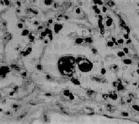

被巨細胞病毒侵害的肺病理生理

醫生診斷巨細胞病毒性肺炎實驗室檢查:周圍血白細胞減少。以呼吸道分泌物、唾液、尿液、子宮頸分泌物、肝、肺活檢標本接種至人胚成成纖維細胞培養基中可分離到巨細胞病毒。呼吸道分泌物和纖維支氣管鏡肺組織活檢標本內發現嗜酸性核內包涵體巨細胞,即能確診。測定血清的巨細胞病毒抗體,雙份血清抗體呈4倍或以上增長時,有助於診斷。